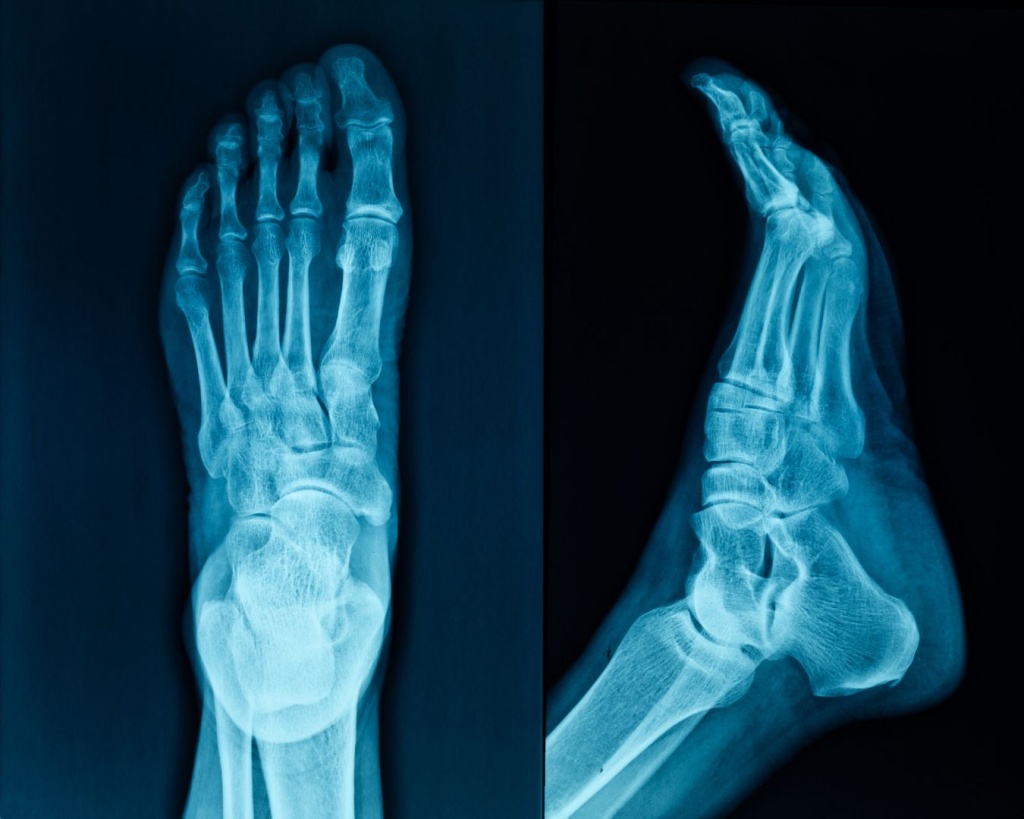

Стопа щодня витримує вагу всього тіла, забезпечує рівновагу та амортизацію під час ходи. Біль, дискомфорт або зміни форми стопи часто сприймаються як тимчасова проблема, але саме вони можуть бути першими ознаками серйозних порушень. Рентген стопи дозволяє оцінити стан кісткових структур і виявити причини болю ще до розвитку ускладнень.

Рентгенографія стопи є одним із ключових методів діагностики при травмах, деформаціях та хронічних навантаженнях, адже вона показує реальну картину розподілу кісток і суглобів у статичному положенні.

Під час дослідження оцінюють:

стан кісток передплесна, плесна та фаланг пальців;

цілісність кісткових структур;

наявність переломів і мікротріщин;

деформації кісток і суглобів;

ознаки дегенеративних змін;

наслідки старих травм;

кісткові розростання;

співвідношення кісток стопи.

Рентген може виконуватися у різних проєкціях, а за показаннями – у положенні з навантаженням, що дозволяє більш точно оцінити функціональний стан стопи.

У Medibor використовується цифровий рентген, який забезпечує високу чіткість зображень і мінімальне променеве навантаження. Такий підхід є особливо важливим для дослідження складної анатомії стопи, де навіть незначні відхилення можуть впливати на ходу та поставу.

Цифрові знімки дозволяють лікарю уважно проаналізувати всі структури стопи та, за потреби, рекомендувати подальші діагностичні кроки або лікування.